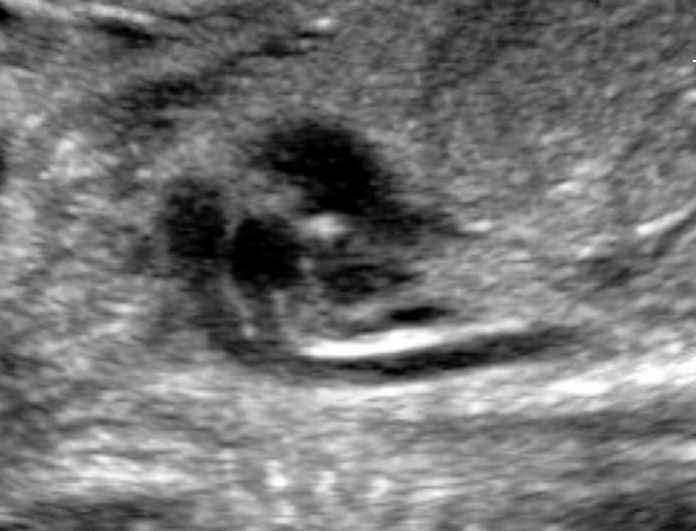

And below a longitudinal view of the same fetus.